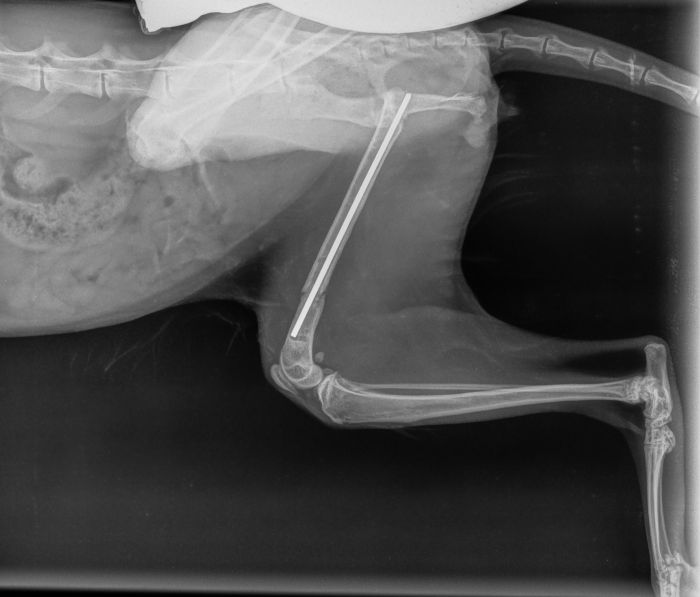

Fixation durch Markraumnägel / Pins

Zusätzlich zur Plattenosteosynthese werden öfters sogenannte Pins oder Markraumnägel verwendet, um einen Bruch in der Längsachse zu stellen.

Fall 1